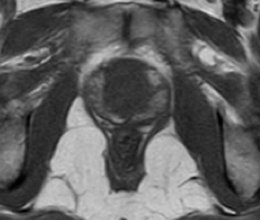

Sequências multiplanares ponderadas em T2 são fundamentais para o estudo da próstata, pois apresentam a maior resolução espacial e de contraste, permitindo avaliação detalhada da anatomia prostática. Nas imagens pesadas em T2, a zona periférica normal tem hipersinal homogêneo, apresentando-se em formato de “crescente” no plano axial. As zonas transicional, central e periuretral, dificilmente diferenciadas por métodos de imagem são, em conjunto, denominadas glândula central ou glândula interna, e exibem intensidade de sinal intermediária em T2. O limite entre a zona periférica e a glândula central é denominado “cápsula cirúrgica”, e a camada fibromuscular descontínua que recobre a glândula, “cápsula prostática”.11(fig. 3).

Figura 3. Imagens de RM ponderadas em T2 demonstrando a anatomia prostática. A) Próstata normal. A zona periférica (ZP) exibe hipersinal homogêneo, e a glândula central (GC) apresenta sinal intermediário. B) Hiperplasia prostática benigna. Observe o aumento significativo das dimensões da glândula central (GC), que exibe sinal heterogêneo e aspecto nodular. O limite entre a zona periférica e a glândula central é denominado cápsula cirúrgica, e linha de baixo sinal circundando a próstata é denominada cápsula prostática (setas).